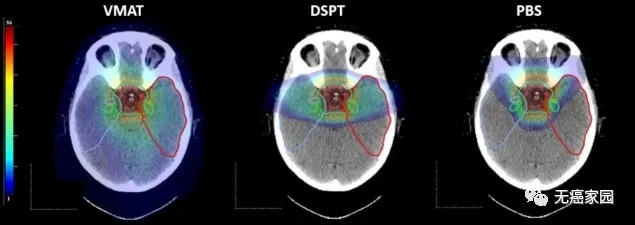

(从左到右)VMAT、DSPT和PBS的剂量分布。目标体积(绿色)以及颞叶和子结构的轮廓。对于记忆功能起关键作用的一个大脑区域是海马体。该研究发现,即使使用DSPT,41%的左侧海马也接受了低剂量的辐射,但是通过PBS治疗可以避免海马体受到辐射,因而记忆功能未受到影响。